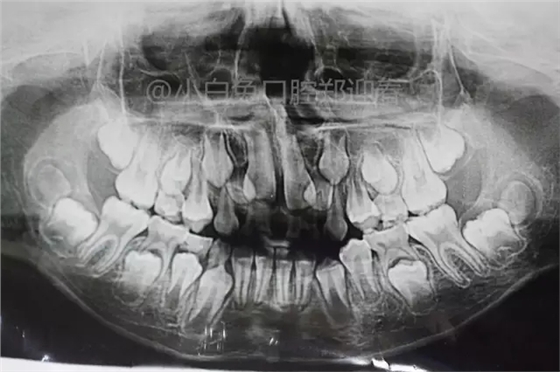

患兒,10歲,因上前牙未替換來(lái)診,查體:輕度反合,51和52、61和62均融合,且存在間隙約4mm,全面曲面斷層片顯示:11、21未萌,52、51、61、62牙根均有不同程度的生理性吸收。

8、乳牙融合牙作X線片檢查時(shí),會(huì)發(fā)現(xiàn)大部分的乳牙融合牙缺失一個(gè)后繼恒牙的牙胚,如乳牙為下頜乳側(cè)切牙和乳尖牙之融合,在其根端應(yīng)當(dāng)有恒牙的側(cè)切牙和尖牙的牙胚,但往往缺一個(gè)恒牙牙胚。而且不論是乳側(cè)切牙和乳尖牙之融合或是乳中切牙和乳側(cè)切牙的融合,所缺的后繼牙牙胚都是恒側(cè)切牙,這可能與恒牙先天性個(gè)別牙缺失中多見(jiàn)于下頜側(cè)切牙有關(guān)。由于融合后的這兩個(gè)雙牙畸形牙,它的牙冠寬度小于兩個(gè)牙的牙冠寬度之和,而影響牙列的大小,尤其在雙側(cè)性乳牙融合牙,對(duì)牙列大小的影響尤大。